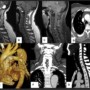

Common origin of Brachiocephalic trunk and left CCA was noted (Arrows).

Figure F: Coronal MIP reformats demonstrate a saccular aneurysm in the spinal canal,at the hairpin bend of anterior spinal artery (Arrow). Note the presence multiple tortuous paravertebral collaterals.

Figure G: Sagittal MIP reconstructions show the saccular aneurysm (Arrow), posterior to C6 vertebral body corresponding to the hypointense lesion on MRI causing cord compression.